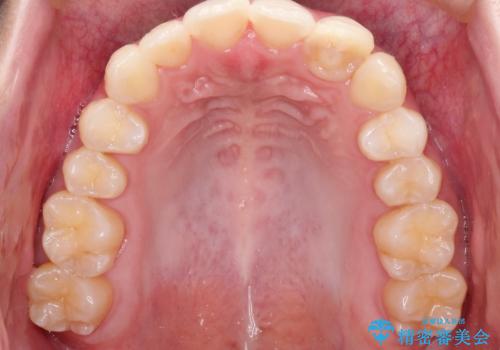

前歯のガタガタを目立たない装置でなおしたい インビザラインによる目立たない矯正

左上の前から2番目の歯が通常とは異なる形態をしており、左右対称にすることはできませんでしたが、インビザラインで周りに気づかれることなく矯正治療をおえることができ、満足していただけました。